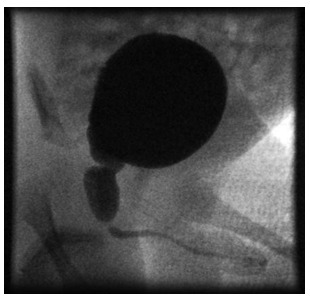

- MCUG is diagnostic and reveals a dilated posterior urethra proximal to a narrowing in the urethra [Figure].

Figure: MCUG in a neonate showing dilatation of posterior urethra with proximal narrowing suggesting posterior urethral valves.